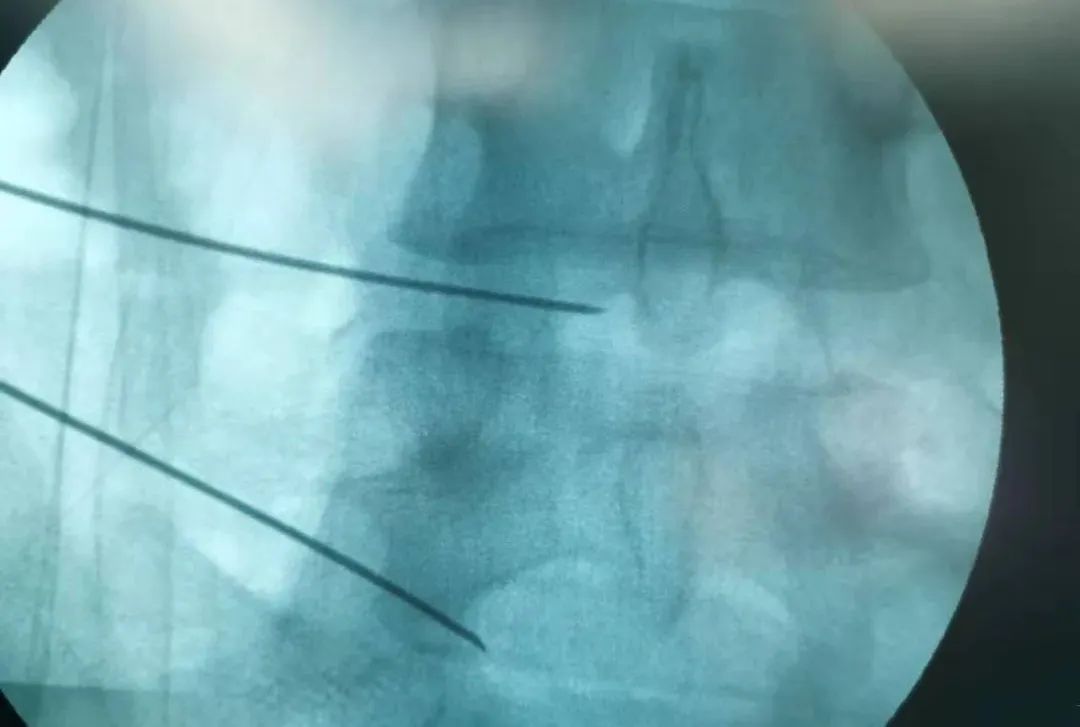

2022年3月15日上午,赵学刚主任为其成功实施了经皮穿刺腰椎间盘射频消融术,手术顺利,术后症状消失,患者自行走回病区。

经皮穿刺腰椎间盘射频消融术

是一种腰椎微创脊柱介入方法

通过专用射频针经过腰椎皮肤

主要从侧方进入椎间盘

一般需要在C臂机监视下

准确达到椎间盘突出的靶点部位

即突出部位

通过专用射频针

直达突出部位